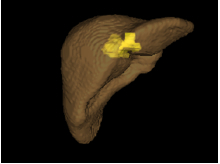

Gefäßbaumrekonstruktion (vollautomatisch)

Der Gefäßbaum der Leber wird auf der Basis der vorliegenden CT Bilddaten rekonstruiert. Dies geschieht vollautomatisch auf der Basis der vorliegenden CT-Bilder. Eine Fusion von arterieller und venöser Phase ist möglich.